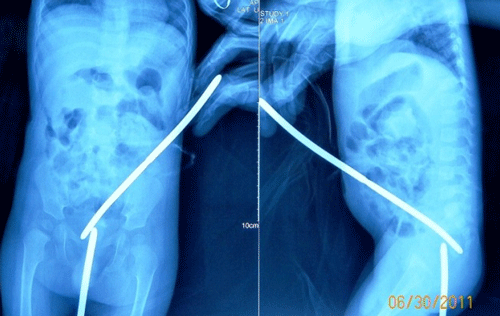

The child was lost to follow up for a year. Per rectal examination revealed that rectum was totally obstructed about 4cm from anal verge. Distal cologram showed complete obstruction of rectum. The rectal obstruction was only few millimeters thick and simulated like congenital rectal atresia (Fig. 1).

Figure 1: Plain roentgenograms with bougies inserted from sigmoid colostomy and anal opening, revealing a thin membranous rectal atresia. |